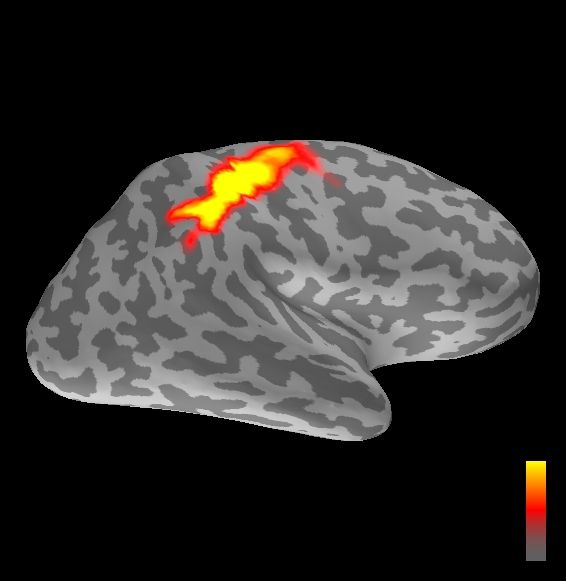

5.2 Results

We applied the ASMC sampler to MEG topographies taken from the above recordings by selecting specific time points according to the previous analysis; the parameter values in the algorithm were the same as those used for the analysis of synthetic data, with the only exception of the noise standard deviation , here estimated from the pre–stimulus interval. In order to validate the results of the ASMC, we also computed source estimates using three other methods: a PF, that approximates the posterior distribution for the current dipoles conditioned on the data up to the selected time point; dSPM, which is based on a distributed source model with an –prior, and consists in normalizing the Tikhonov regularized solution by the noise standard deviation; and sLORETA, which is similar to dSPM but is claimed to have a smaller localization bias. Figure 4 shows the results at , and ms after the stimulus onset. The results are visualized on a computer representation of the brain obtained by “inflating” the cortical surface: gray levels contain the anatomical information, light gray representing gyri and dark gray representing sulci; the activity estimate is coded in color scale, increasing from red to yellow. Importantly, this visualization allows activity in the sulci to be clearly visible; on the other hand, since neighbouring volumes may be moved apart by the inflation process, distinct activity regions are often due to underlying volumetric masses that are very close to each other.

Before describing the results, let us comment on the qualitative difference between the images produced by the ASMC sampler and the PF, on the one hand, and those produced by dSPM and sLORETA, on the other. First of all, we point out that all the quantities shown in the images of Fig. 4 are somehow related to the probability of activation at specific locations. Indeed, for both the ASMC and the PF we plot the approximation of the intensity measure (3.8); for any single grid point, this value can be interpreted as the probability of a dipole being at that location, while it integrates, over a given volume , to the mean number of dipoles within . As for dSPM, the represented quantity is a statistical value that is –distributed under the null–hypothesis of zero activity; as a direct consequence, it also yields a probability of activation, which is however not constrained to be dipolar. Similar considerations apply to sLORETA, although with a different statistical distribution. Importantly, the representation of the results is clearly affected by the setting of the visualization threshold. Owing to the explained differences between the methods, it seems reasonable to use a different value for each method. At the same time, since the plotted quantity is a probability of activation, it seems right to use the same thresholding for different time points. In this connection, the thresholds in Fig. 4 have been chosen by hand following the guidelines just outlined.

Using the same thresholding and parameters at different time points makes the four methods respond differently to the diverse intensities of the different sources. Whenever a stronger source is active, both sLORETA and dSPM will tend to produce widespread estimates, while weaker sources will be represented as small active areas. The behaviour of the ASMC and of the PF is the opposite: a stronger signal will lead to a precise localization of a dipolar source, and then to a focal marginal distribution for the location; a weaker signal will translate to higher uncertainty on the source position, and therefore a more widespread posterior map.

The phenomenon just described is indeed clearly visible in Figure 4. At ms, all the methods correctly identify the rather strong activation in the contra–lateral primary somatosensory cortex: the ASMC and the PF provide very focal maps, while dSPM and sLORETA provide compatible widespread estimates; dSPM also exhibits a more posterior peak which does not fit with the commonly agreed models of the response to median nerve stimulation; this may be due to the formerly described brain inflation.